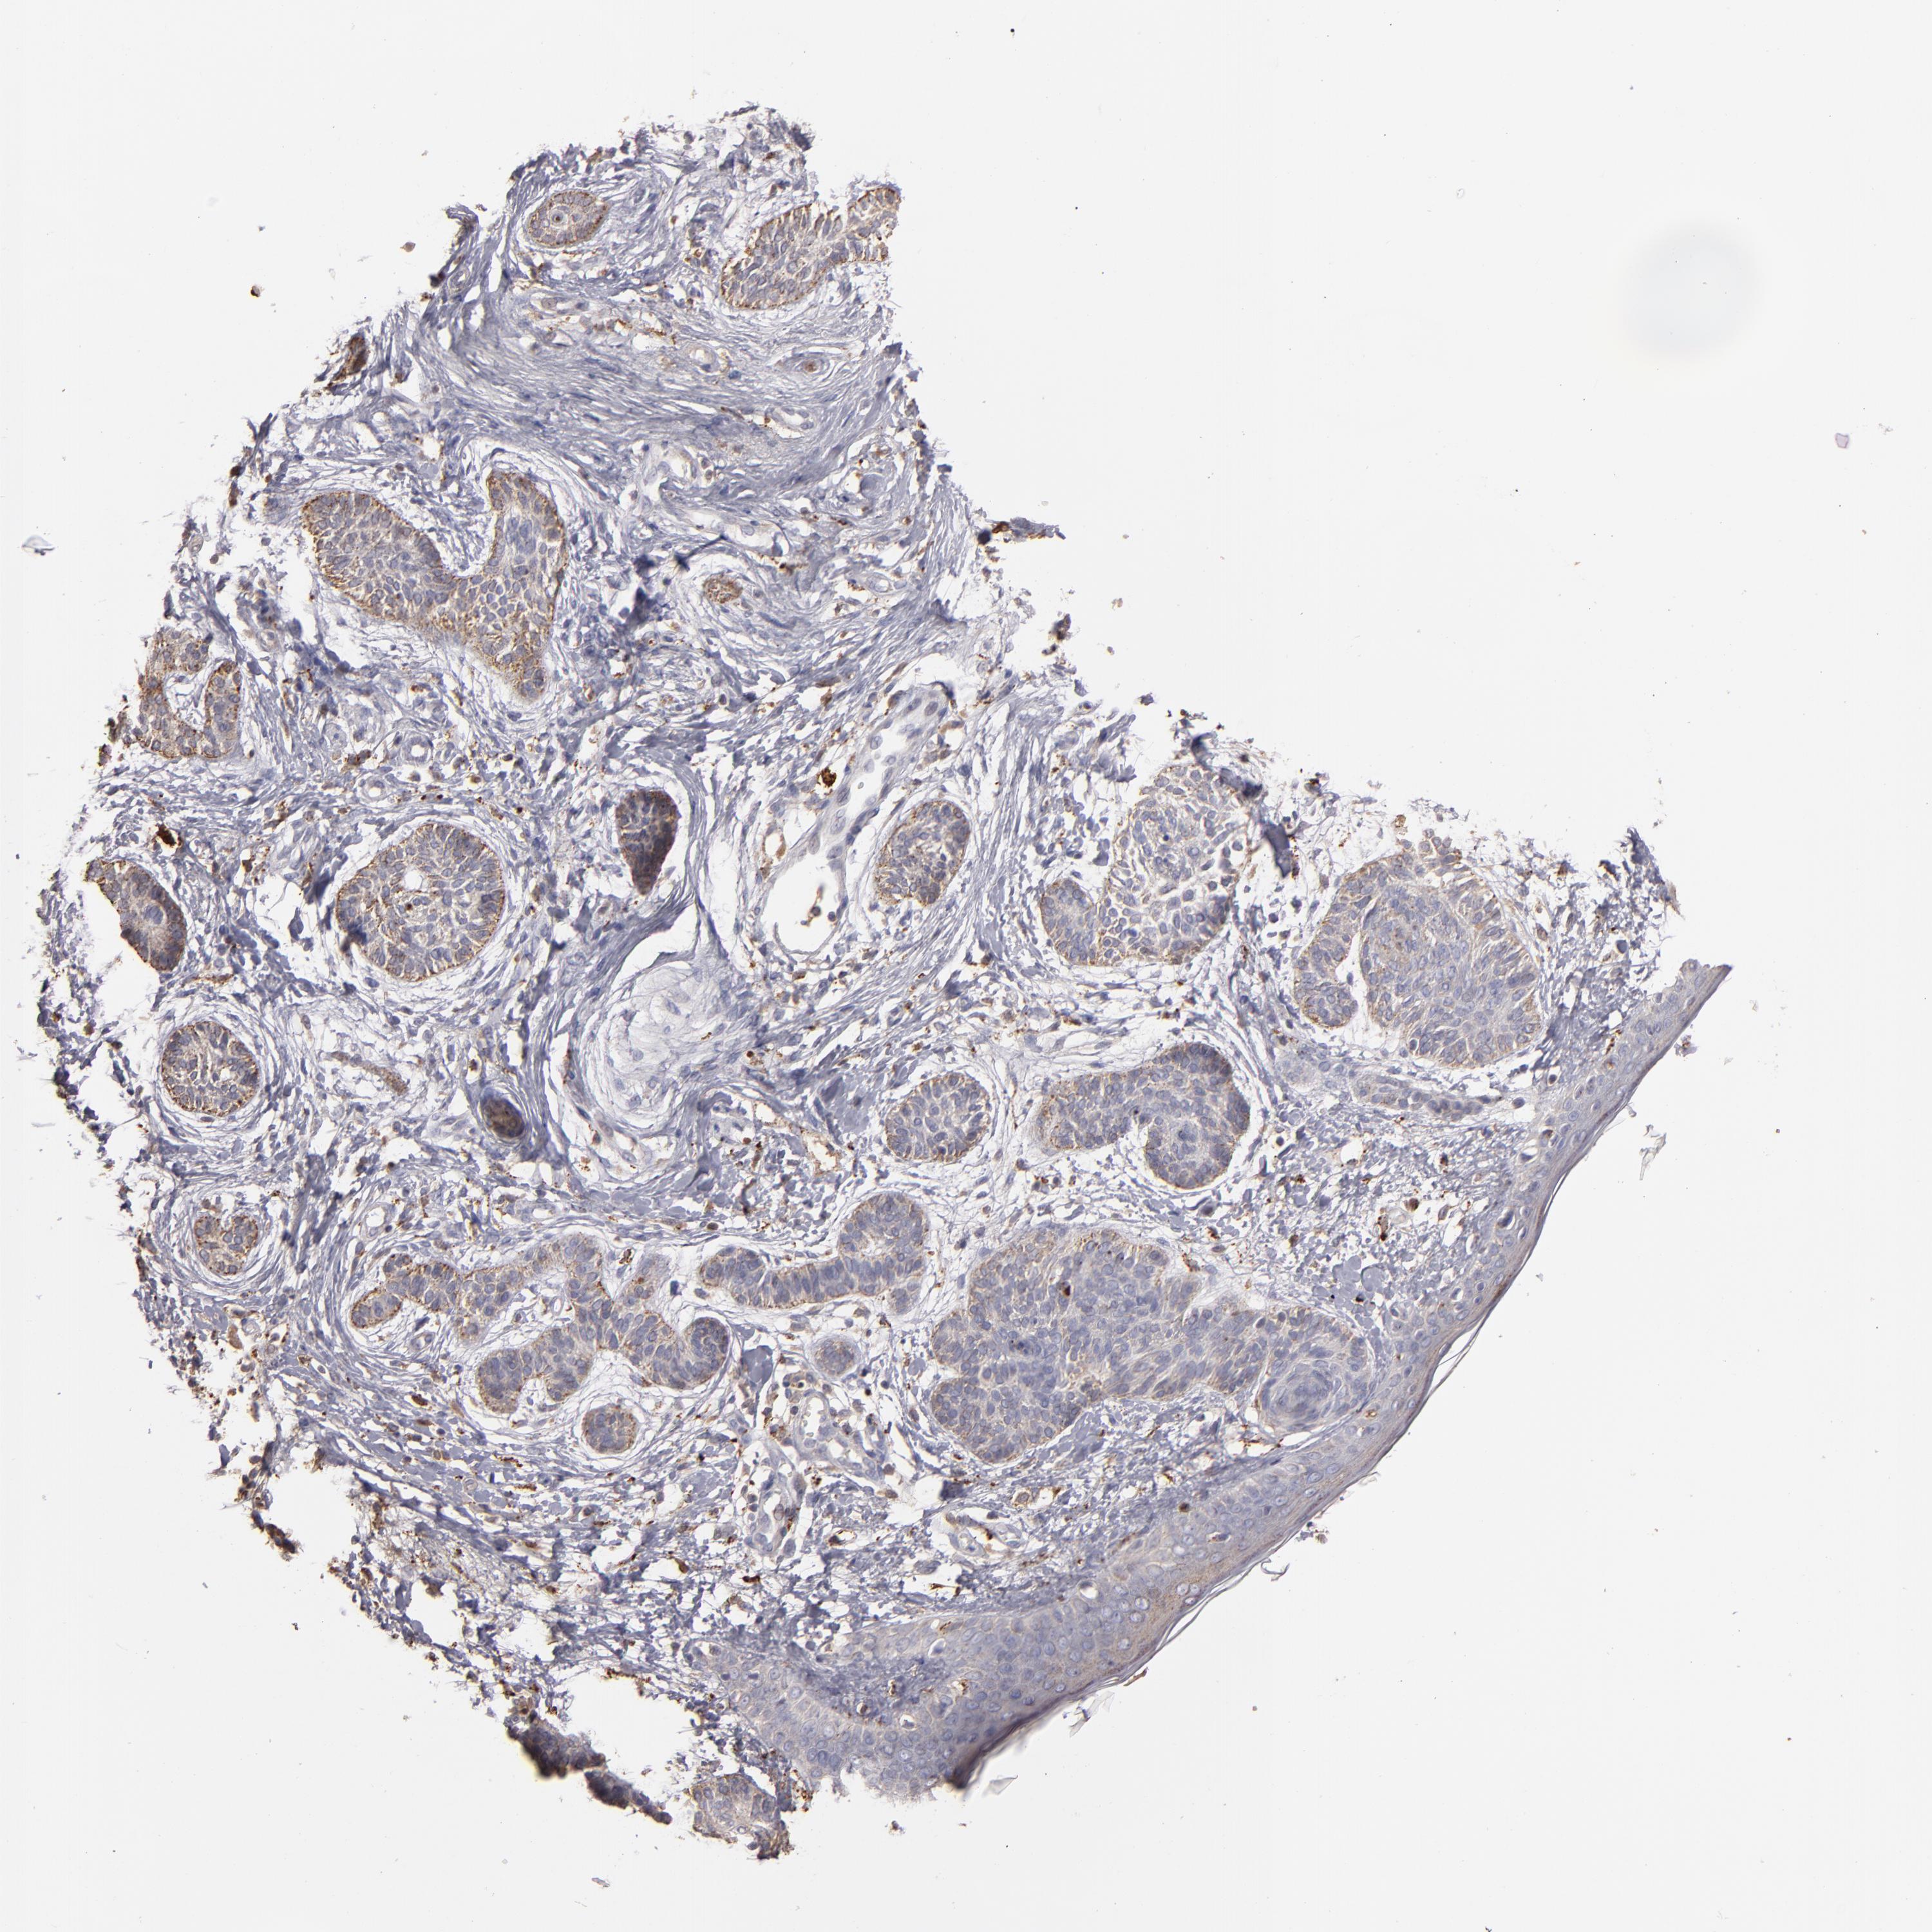

Basal cell and squamous cell cancer

SKIN CANCER - Protein expressioni

A mouse-over function shows sample information and annotation data. Click on an image to view it in a full screen mode. Samples can be filtered based on level of antibody staining by selecting one or several of the following categories: high, medium, low and not detected. The assay and annotation is described here.

Antibody stainingi

Antibody staining in the annotated cell types in the current human tissue is reported as not detected, low, medium, or high, based on conventional immunohistochemistry profiling in selected tissues. This score is based on the combination of the staining intensity and fraction of stained cells.

Each image is clickable and will lead to virtual microscopy that enables deeper exploration of all samples and also displays staining intensity scores, fraction scores and subcellular localization as well as patient and tissue information for each sample.

Antibody HPA001852

Staining

High

Medium

Low

Not detected

Intensity

Strong

Moderate

Weak

Negative

Quantity

>75%

75%-25%

<25%

None

Location

Nuclear

Cytoplasmic/membranous

Cytoplasmic/membranous,nuclear

Squamous cell carcinoma, NOS